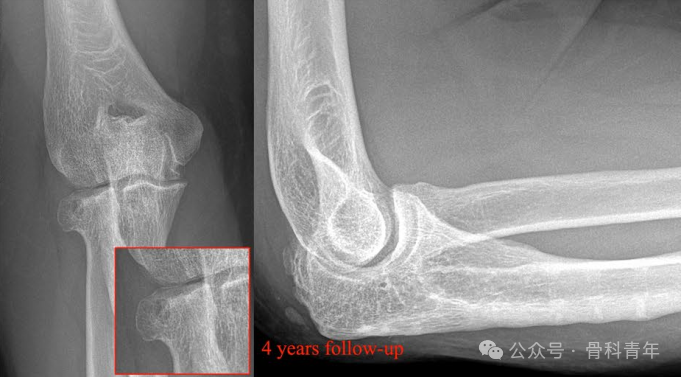

病例3:后孟氏骨折,桡骨头骨折采用2枚可吸收螺钉固定。